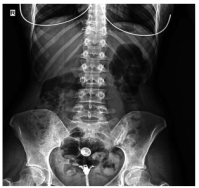

Dose reduction was used in patients with moderate and severe back pain, constituting 37.2% of the patients describing the complaint. The vast majority of these patients responded to dose reduction, while eight (10.2%) patients needed to use non-steroidal anti-inflammatory drugs for pain relief. Sacroiliitis was present in four (4%) patients, including three females and one male. There was no statistically significant difference between the sexes for sacroiliitis development (p=0.25). Bilateral sacroiliitis was detected in one patient (Figure 1). Sacroiliitis regressed 1.5 to 2.5 months after isotretinoin treatment cessation in all patients. The patients diagnosed with sacroiliitis were followed for six months. Three (3%) patients described myalgia, which was of mild severity and did not require additional treatment. Among these patients, two female patients also described low back pain. Creatine kinase (CK) elevation was observed in 18 (18.1%) patients, including 13 males and two females, one to three months after the beginning of treatment (p=0.1). The elevated CK values ranged between 233 and 940 IU and returned to normal levels after dose reduction. One (1%) female patients who was on low-dose isotretinoin treatment (0.5 mg/kg) was diagnosed with enthesitis at three months of treatment (Figure 2).

Sacroiliitis is the inflammation of the sacroiliac joint and can be seen as a component of various rheumatic diseases including psoriatic arthropathy, familial Mediterranean fever, and Behçet’s disease.[27,28] Acute sacroiliitis can also develop secondarily to hyperparathyroidism, gout, calcium pyrophosphate dihydrate deposition, infectious factors such as brucellosis, hematological malignancies, and intravenous drug use.[28] In this study, the patients having a history of such diseases associated with sacroiliitis were excluded. Isotretinoin-induced sacroiliitis develops days to weeks after starting the treatment.[29] The presence of human leukocyte antigen-B27 (HLA-B27) may also pose a tendency toward the development of sacroiliitis during isotretinoin treatment.[30] In a study by Baykal Selçuk et al.,[3] the prevalence of sacroiliitis during isotretinoin use was found to be 8.2% and the symptoms developed within the first two to three months of isotretinoin treatment. In the current study, sacroiliitis developed within the first one to six months of isotretinoin treatment. Similar to the study by Baykal Selçuk et al.,[3] there was no significant difference between both sexes in terms of sacroiliitis development. Another study reported that sacroiliitis related to isotretinoin treatment was more frequent in females than males.[23] Since the number of patients diagnosed with sacroiliitis is low in our study, future studies with larger series would be more helpful in determining the sex predominance for sacroiliitis development during isotretinoin treatment.

Previous studies provide insufficient data to assume that sacroiliitis development is dosedependent. Karadağ et al.[29] reported sacroiliitis in four patients undergoing isotretinoin treatment at a dose of 0.5 mg/kg. The patients developing sacroiliitis in our study were also on a low dose of isotretinoin, supporting the notion that sacroiliitis development is not dose-dependent. The lower rate of sacroiliitis in the current study can be attributed to the careful selection of patients with no prior history of arthritis or arthralgia, as well as the heterogeneity of the genetic features of the study populations that can determine the susceptibility for the development of sacroiliitis. In our study, symptoms completely regressed with treatment cessation in all patients with sacroiliitis.